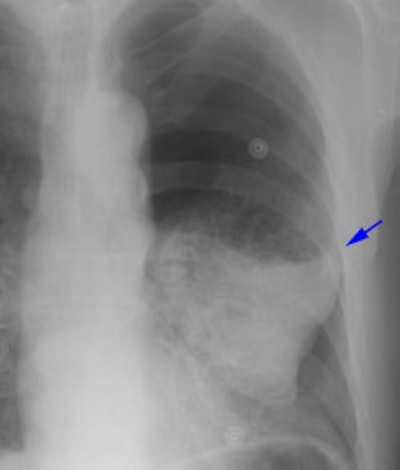

Example 2: This patient had a large peripheral squamous cell carcinoma that had a long area of contact with the chest wall on CT (Click here to view the patients CT scan). Following percutaneous biopsy of the mass the patient developed a large left pneumothorax. Although the left upper lobe collapsed, it did not completely fall away from the chest wall (blue arrow) increasing the concern for chest wall invasion in this case. At surgery, visceral pleural invasion was found, but there were only fibrous adhesions between the visceral pleura and the chest wall. There was no parietal pleura or chest wall invasion. Benign pleural adhesions are a cause of false-positive results when assessing for chest wall invasion with iatrogenic pneumothorax.

08290111235947 Chest Wall Pre Ptx S

08290111240068 Chest Wall Post Ptx S